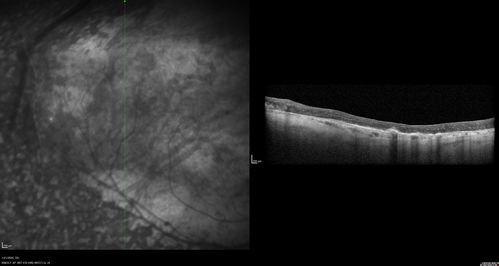

Enhanced S Cone Syndrome - Goldmann Favre - NR2E3 Mutation

82 year old man with poor vision for many years. VA HM OD, 5/200 OS. Diagnosed at age 12 with retinitis pigmentosa. Nystagmus.